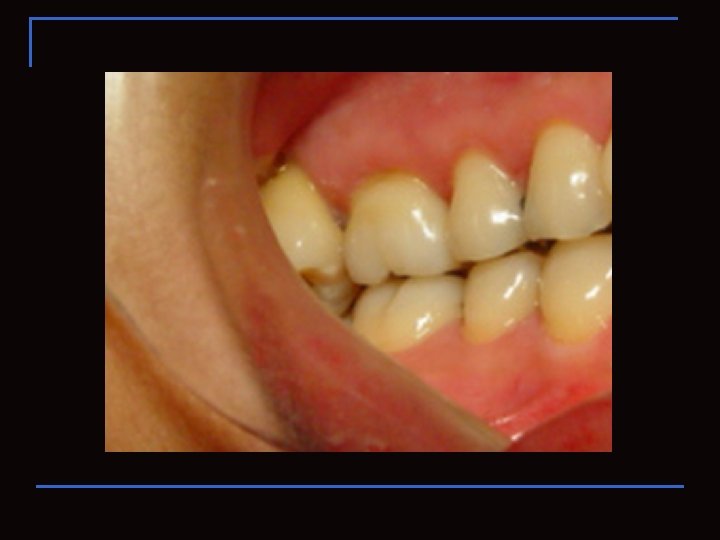

OCLUSIÓN n n ESTÁTICA DINÁMICA ( Fase V )